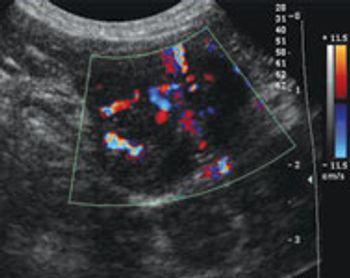

FLUTD refers to a spectrum of diseases that result in pollakiuria, hematuria, stranguria, dysuria and/or periuria in the cat.